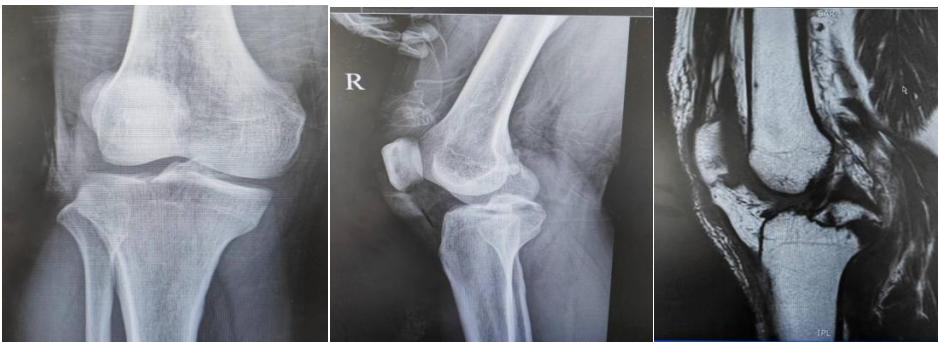

术前x线及磁共振

近日,一中年男性患者因车祸导致左侧胫骨平台后交叉韧带止点撕脱骨折,骨折块移位,影像表现Meyers-McKeever Ⅲ型骨折。骨二科业务主任吕荼团队成功为其实施全镜下 Endo-Button 固定后交叉韧带胫骨撕脱骨折复位及微钢板内固定术。相较传统开放性手术,该技术对膝关节的组织结构损伤小,能够降低神经损伤、术后关节瘢痕粘连及功能障碍的风险,术后膝关节功能恢复较好。

后交叉韧带断裂附带胫骨止点骨折在临床上较常见,通常为强大能量损伤所致,发病率约占急性膝关节损伤的 3%~4.5%,是一种特殊损伤类型。损伤后的后交叉韧带止点撕脱骨折的骨折端向上、前方移位,骨折端常被周围软组织嵌顿,保守治疗骨折块不能复位,很容易出现骨折不愈合、畸形愈合,从而导致膝关节不稳及疼痛,继发半月板损伤、软骨损伤,远期导致膝关节骨关节炎。目前对于后交叉韧带胫骨止点撕脱骨折骨块移位的患者尚无统一的手术治疗方案,常规的治疗方案有开放性手术及关节镜下微创手术方案。最近一项涉及 637 例患者的系统资料回顾,与开放手术相比,关节镜下手术治疗患者的客观和主观膝关节预后得分更高。